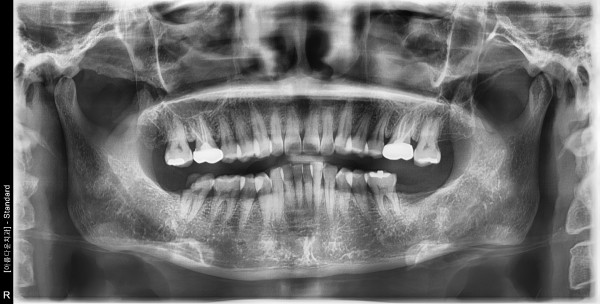

53세 여자 하악 구치부 뼈이식 후 임플란트 식립